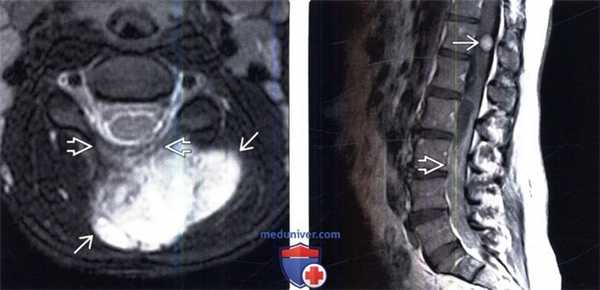

(Слева) Аксиальный срез, FS Т2-ВИ: крупное неоднородное гиперинтенсивное образование, представляющее собой ЗООПН, растущую в паравертебральные ткани шейной области из ветви задней первичной ветви спинномозгового нерва и сопровождающуюся инфильтративно-деструктивными изменениями дуги позвонка.

(Справа) Сагиттальный срез, Т1-ВИ с КУ: крупная диффузно накапливающая контраст интраспинальная ЗООПН, распространяющаяся по каналу от уровня L1-2. На уровне Т12 видна небольшая четко ограниченная нейрофиброма.